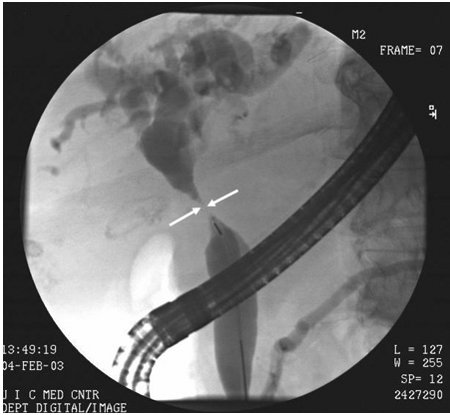

Colangiocarcinoma

Imagem de colangiopancreatografia retrógrada endoscópica (CPRE) de colangiocarcinoma do ducto hepático com estenose do ducto (setas)

Do acervo de Dr. Joseph Espat; usado com permissão